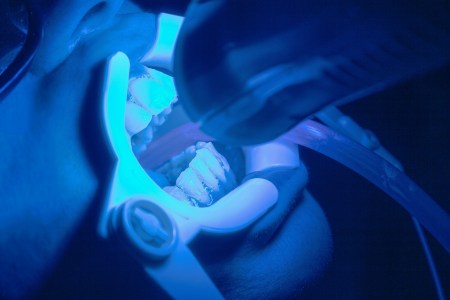

Da li je izbeljivanje zuba štetno?

Izbeljivanje zuba se vrši hemijskim putem uz pomoć polimerizujuće lampe ( lasera ) koji samo podstiču hemijsku reakciju, ali ne učestvuju...

Da li je izbeljivanje zuba štetno

Izbeljivanje zuba se vrši hemijskim putem uz pomoć polimerizujuće lampe ( lasera ) koji samo podstiču hemijsku reakciju, ali ne učestvuju u samom procesu izbeljivanja...